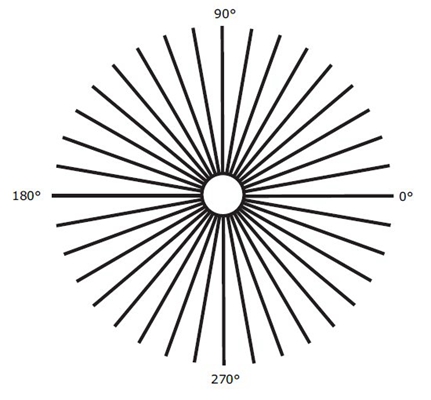

A:判斷自己有沒有散光,最簡單的方法是使用散光表來測試。散光表是一種簡單、方便的方法,但是它的準確度不是特別精確。在配鏡的情況下一般再用裂隙法,或者是交叉圓柱鏡法來精調散光的度數。散光表在網上可以看到,它類似於鐘錶的盤面,有12個數字。各個鏡線……